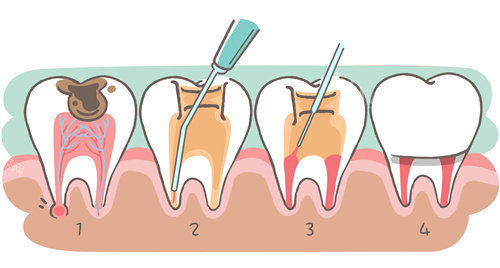

二、治疗流程:四步保住快烂穿的门牙

头一步:精细诊断,明确根管状态

3D口扫+显微镜探查:使用德国卡瓦CBCT获取牙根三维影像,结合显微镜放大20倍观察根管内部结构,判断牙根是否穿孔、钙化或折裂;

第二步:清创,杜绝二次感染

超声根管预备:利用超声波震荡去除根管内坏死组织、细菌及牙本质碎屑,比传统器械清洁效率提升40%;

激光消毒:采用Er:YAG激光对根管壁进行灭菌,可穿透牙本质小管0.5mm,杀灭99.9%的顽固细菌;

技术亮点:益众口腔优先引入“根管三维充填技术”,通过热牙胶垂直加压充填根管,确保侧支根管无渗漏,避免术后疼痛。

第三步:修复穿孔,重建牙根结构

第四步:美学修复,改善自然外观

纤维桩+全瓷冠:根管治疗后,采用玻璃纤维桩增强牙根强度,外接二氧化锆全瓷冠,其透光性与天然牙相近,避免“假牙感”;